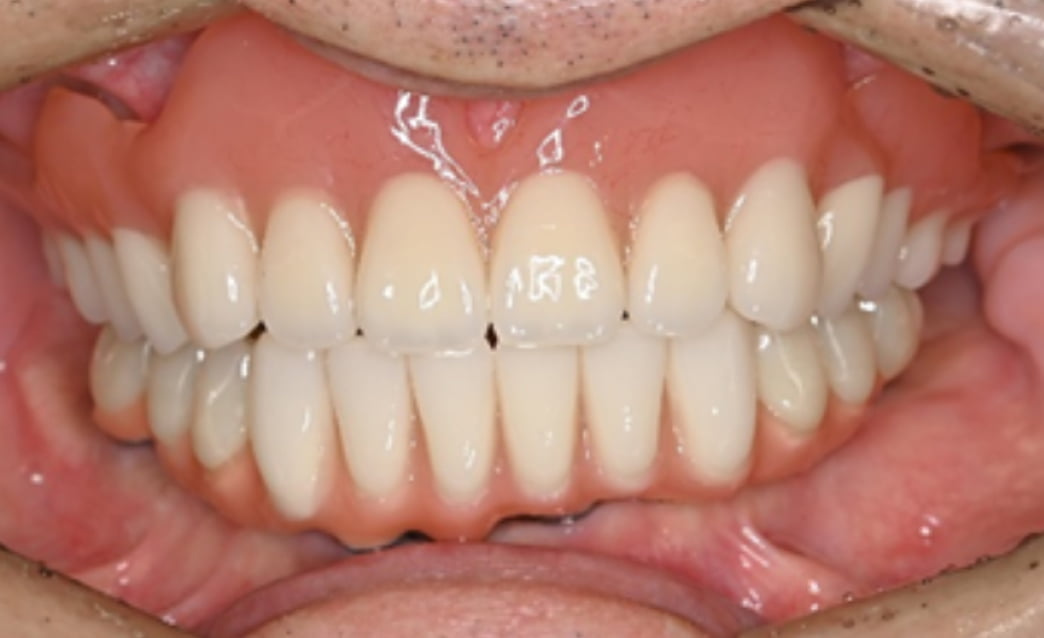

60代

Before

After

| 主訴 | 入れ歯が合わない。 |

| 治療内容 | 下顎の残存歯は、歯周病が進行していたため全て抜歯をおこない、同日にインプラント埋入と仮歯の装着をしました。骨とインプラントが固定されるのを約3ヵ月待ち、型どりをして最終補綴を装着します。上顎にはノンクラスプデンチャーを使用し、快適に食事がとれています。 |

| 治療期間 | 6ヵ月 |

| 費用 | ¥3,586,000(税込み) |

| リスク・副作用 |

外科処置が必要。コストがかかる。 |